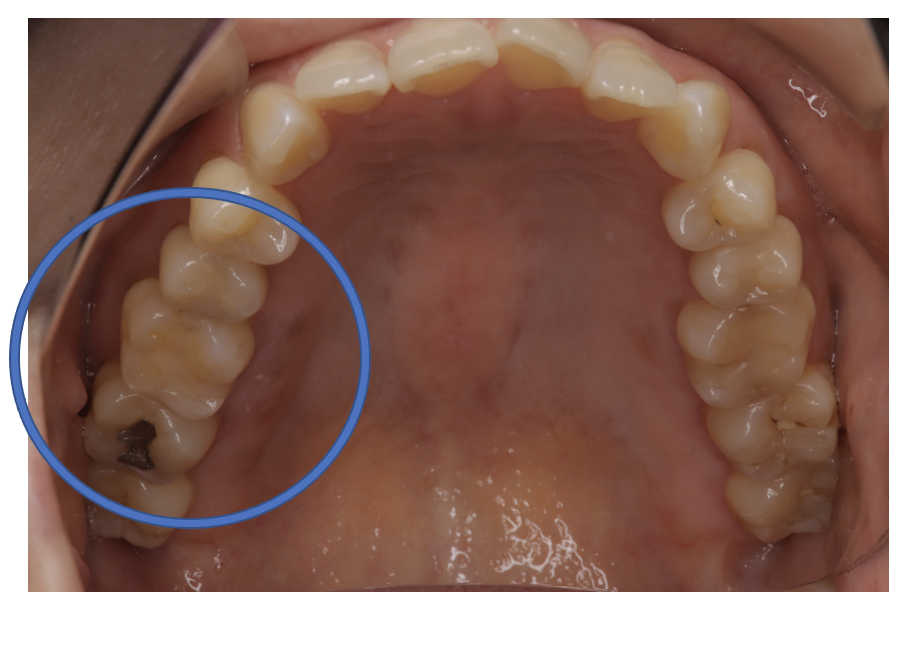

フルジルコニアCr 18 No.44

Before

| 治療方法 | フルジルコニアCr 虫歯などで失った歯質を天然歯と同じ色・質感のセラミックの一種であるジルコニア(人工ダイヤモンド)で補う治療法。 |

| 治療のデメリット | 変色がなく耐久性の高い治療ですが、歯周病や二次虫歯を予防するためには歯科医院での定期的なメインテナンスが大切です。 |

| 費用 | ¥89,000 |

| 通院回数 | 1ヶ月〜6ヶ月 |

| 備考 | 院長より プラスティック修復部の内部に虫歯が進行してしまっていたケースです。中を開けて見てみると、外から想像するよりもはるかに虫歯が 広がってしまっていました。幸運にも神経を保存できたので、生きた臓器としてまだ使うことが可能です。残存歯質がかなり薄く弱くなってしまったので、ジルコニアで被せて守ってあげています。 |